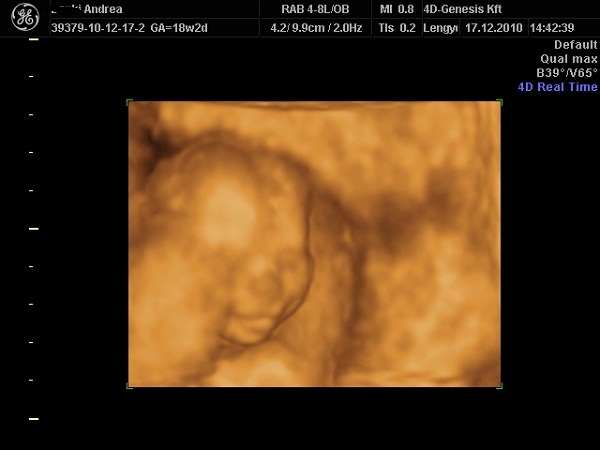

Meglett a genetikai szűrésem eredménye:

A vizsgált markerek eredménye: PAPP-A szint:

724.00

miu/L

0.90

MoM Szabad ß-hCG szint:

24.30

Ng/ml

0.68

MoM Tarkóredő vastagsága (NT):

2.00

mm

1.33

MoM A szűrővizsgálat eredménye: negatív

Kockázat a Down-kór előfordulására: 1 : 9 700

Kozkázat a 18-as triszómia (Edwards-kór) előfordulására: kevesebb mint 1 : 50 000